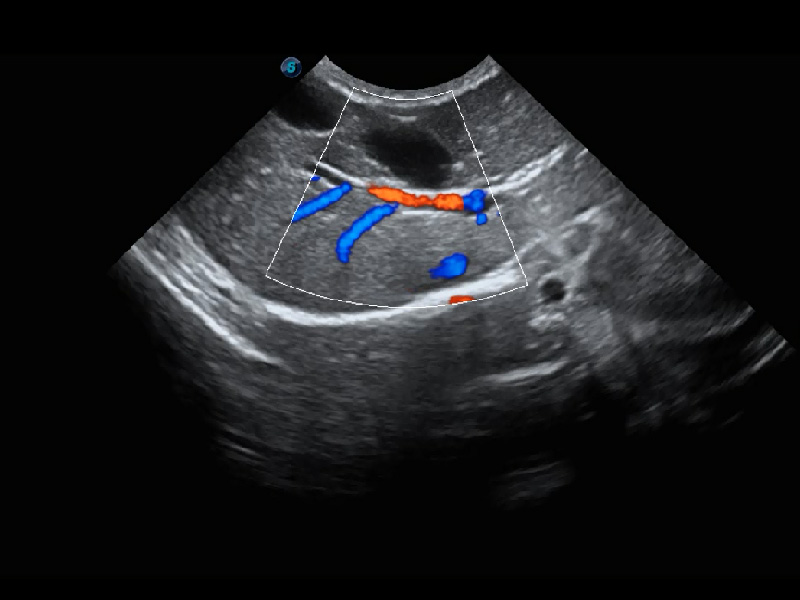

4T血流成像 微察秋毫

融合不同血流成像技术的优势,即可以提升血流成束性,同时可提高血流的视觉敏感性。

PDI 能量多普勒血流

提供高灵敏度和空间分辦率的血流图像,获得更加真实和丰富的诊断信息。

SR Flow 高分辨率血流成像

能够清晰显示细小、低速血流图像,获取传统彩色多普勒技术难以得到的细节和信息。

优异的基础图像

(犬)肾脏血流